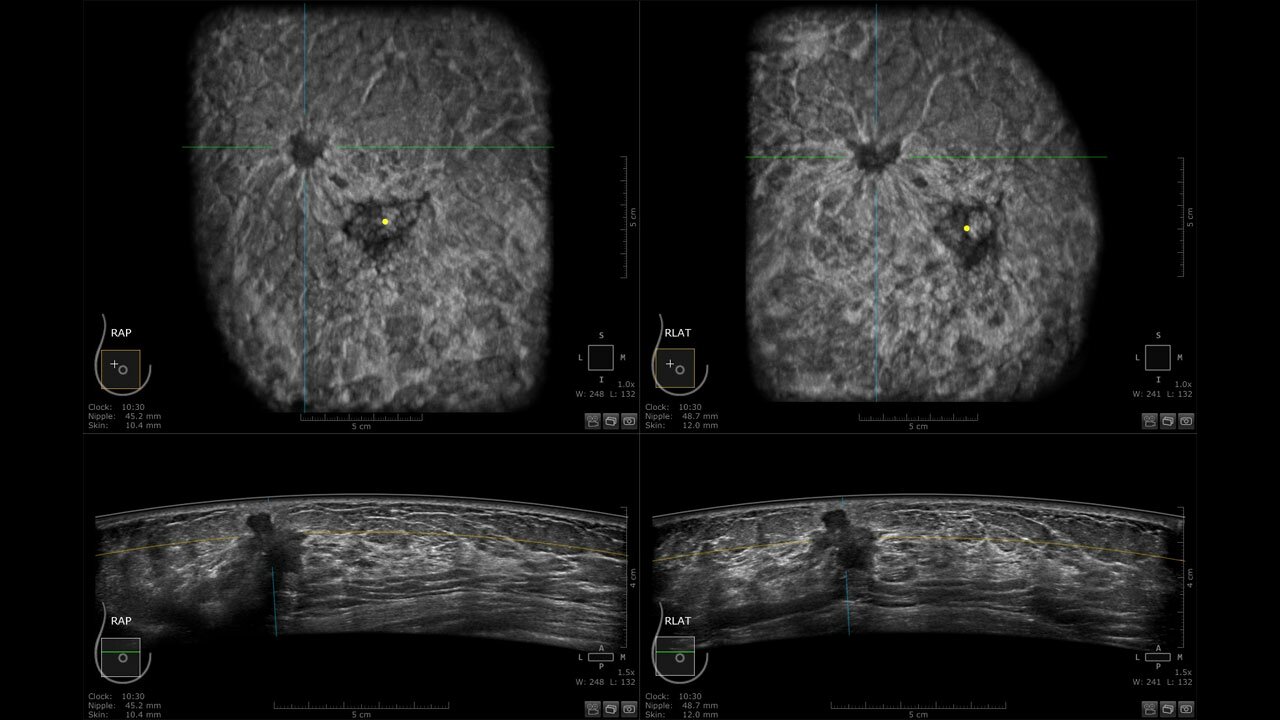

Клинические изображения

• Отображение объемных 3D ультразвуковых изображений, которые состоят из традиционных поперечных и воссозданных коронарных и сагиттальных проекций

• Возможность отображения полного 3D изображения

• Стандартизованная ориентация изображения:

• "толстый срез" в коронарной плоскости;

• поперечная;

• сагиттальная плоскость;

• радиальный и антирадиальный поворот изображения;

• Одновременный просмотр двух изображений для сопоставления в коронарной плоскости